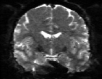

Refer to captionRefer to captionRefer to captioninitializationOptimal TransportRefer to captionRefer to captionRefer to captionOptimal Transport (blurred)Refer to captionRefer to captionRefer to captionMultilevelRefer to captionRefer to captionRefer to captionoptimizedRefer to captionRefer to captionRefer to captionRefer to captionRefer to captionRefer to caption

Figure 6: Example field maps (Subject ID 826353) at initialization (top row) and after optimization with Gauss-Newton (bottom row). The first column uses the proposed optimal transport initialization scheme. The middle column uses the same scheme with an additional Gaussian blur to promote smoothness. The right column uses the coarse-to-fine multilevel initialization scheme from HySCO with five levels, and the final field map is optimized at the original image resolution. The multilevel initialized field map is smooth by construction and further optimized to improve the relative image distance at the full resolution. The optimal transport initialization accurately corrects the distortions but is not smooth in the non-distortion dimensions unless blurred with a Gaussian. After the fine-level optimization all field maps are visually similar.